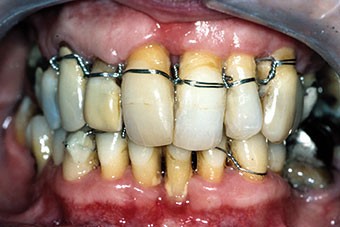

Une patiente âgée de 45 ans consulte à la fin des années 1990 avec une contention en échelle au maxillaire afin de soulager les mobilités des dents antérieures.

Les examens cliniques et radiographiques montrent une parodontite chronique généralisée (fig. 1a à m).

La patiente, en bonne santé, ne fume pas.